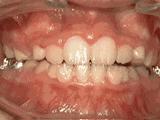

第四种:

牙列拥挤,牙槽骨过窄,牙齿没有足够空间,只好前后左右高低上下乱长,经过矫正后的牙齿是这样的~